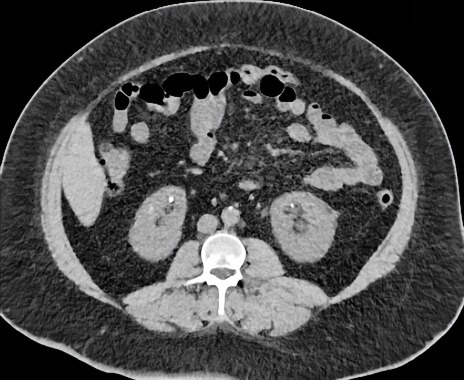

Le scanner révèle la présence d'un calcul mesurant 3 mm localisé au niveau de la jonction urétéro-vésicale gauche avec une dilatation de l'uretère gauche en amont, accompagnée d'une ectasie du bassinet rénal. Par ailleurs, l'examen met en évidence plusieurs calculs caliciels de façon bilatérale, qui ne présentent pas de caractère obstructif. On remarque sur la coupe présenté l’aspect en éponge des calices.